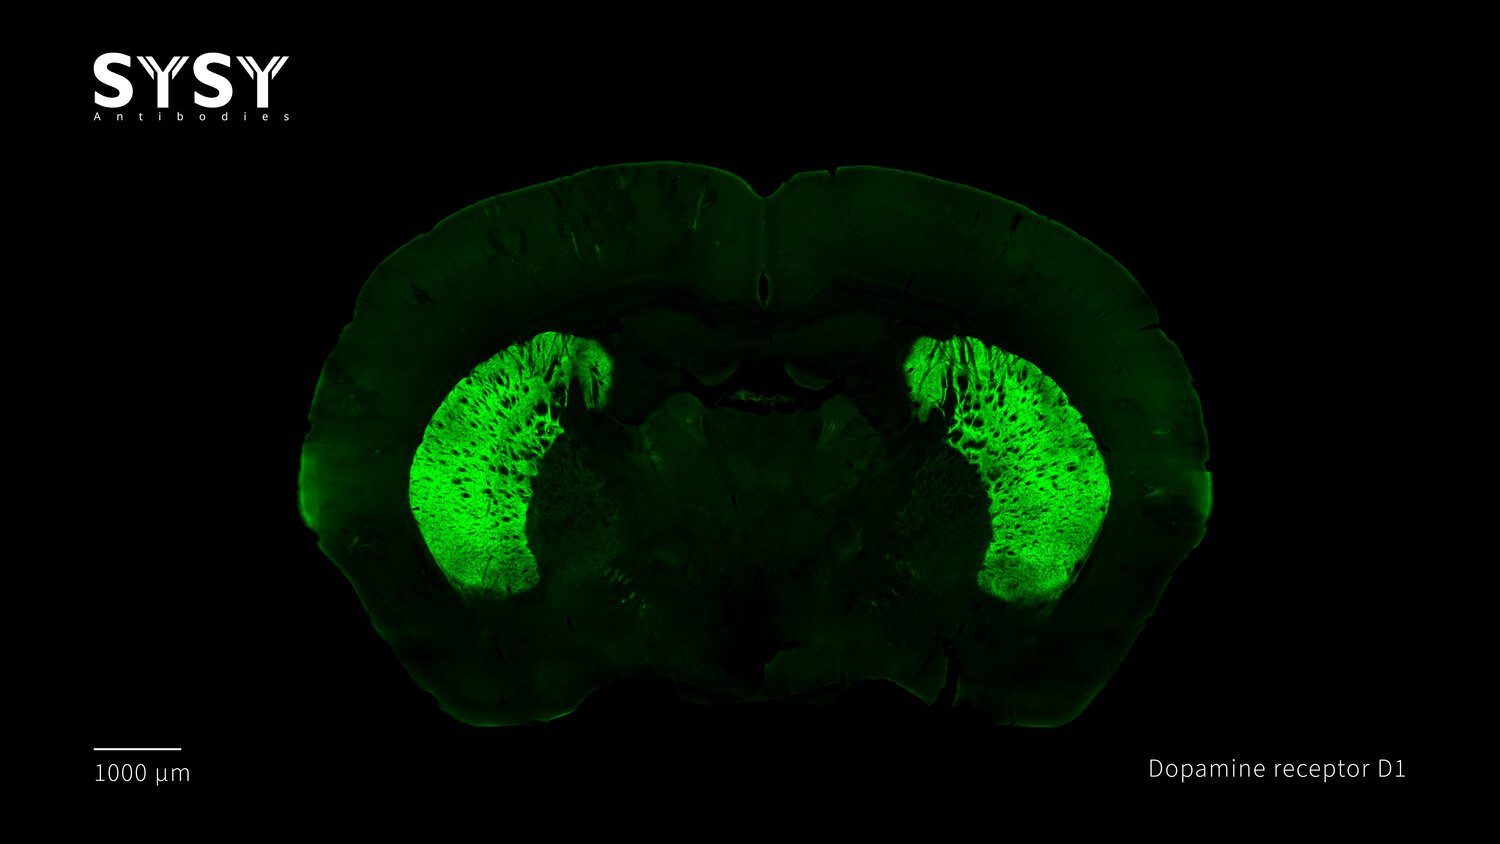

Dopamine receptor D1

Indirect immunostaining of a formaldehyde fixed coronal mouse brain section with rat anti-Dopamine receptor D1 antibody (cat. no. 376 017, dilution 1 : 500).